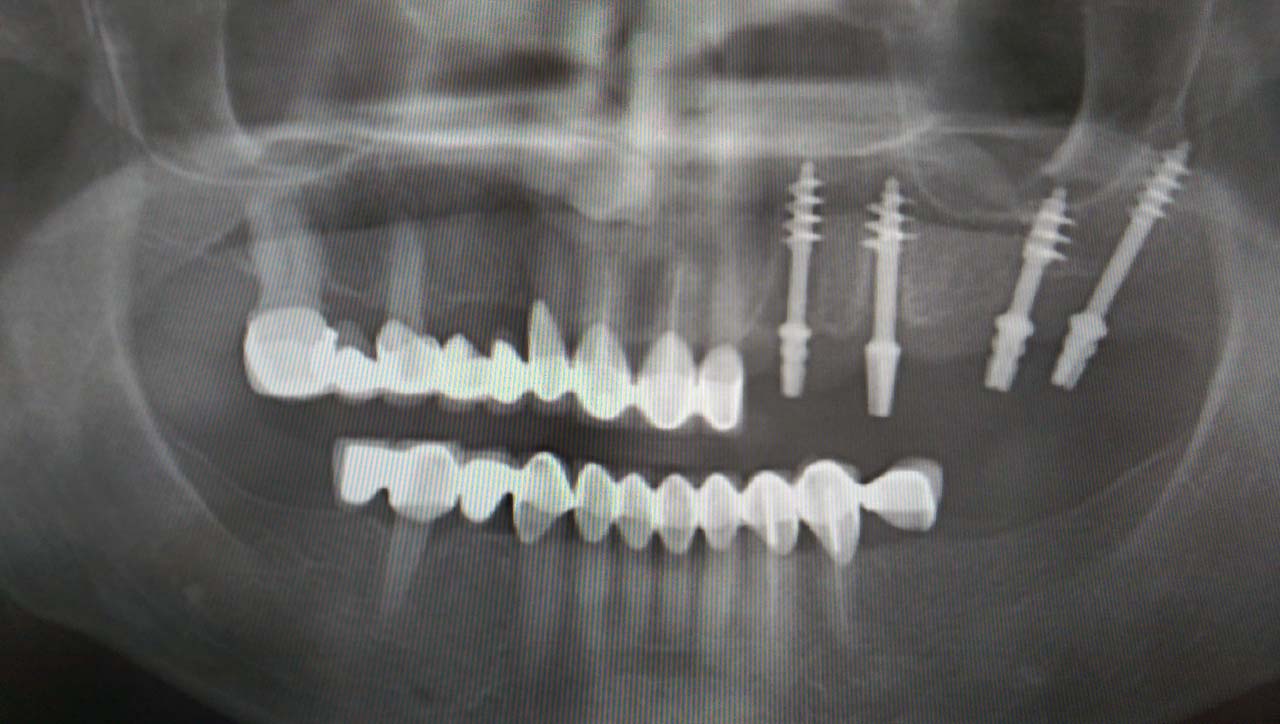

Elhanyagolt fogsor cseréje 2 nap alatt

2 nap alatt varázsoltuk ezt a szép esztétikus alsó, felső körhídat implantátumokkal megtámasztva a korábban elhanyagolt szájba. Az 1. nap 26 fogat távolítottunk el, mert annyira rossz állapotban voltak, és rögtön azonnal terhelhető IHDE svájci implantátumokat raktunk be, fentre 8, lentre 6 darabot. A sebeket összevarrtuk és intraorális szkennerrel digitális lenyomatot vettünk. 2 nap múlva pedig beragasztottuk a kész PMMA műanyag körhidakat. Dr. Kelemen Péter és a Symbion Fogtechnika munkája.